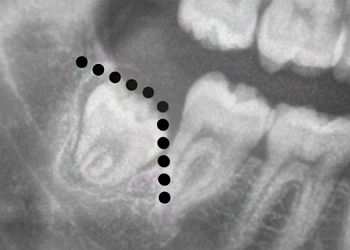

Explore 75+ detailed third-molar case studies, organized by difficulty to sharpen your diagnostic skills and guide case selection. Learn key red flags and follow step-by-step walkthroughs for efficient, predictable extractions.

The O.S. Accelerator course gradually builds your confidence and skills in a step-by-step progression assuming no prior knowledge of third molar extractions.  Upon completion of the third molar content, you'll instantly be able to recognize cases that can be managed vs. those that should be referred.  You will also instantly recognize the approach to take and instruments to use for the common types of impactions including mesioangular, distoangular, horizontal, and vertical.